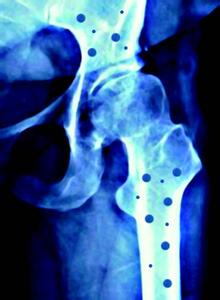

青年妇女由于生育和哺乳需要大量的钙,微量元素检测仪厂家分析如果未能及时补充,不仅不能进行正常的骨钙化,还会加快骨的吸收,使骨骼中矿物质减少;加上多次妊娠、哺乳,骨骼脱钙越来越严重,就可能导致软骨病。软骨病最常见的症状是骨痛、肌无力和骨压痛,有时候也有肌痉挛及手足抽搐;或表现为骨质软化、容易变形,孕妇骨盆变形可致难产。软骨症发病初期,骨痛部位不固定,多在腰背部或下肢,一般活动时加重,常被认为是风湿或神经官能症。肌无力也是一个重要表现,开始是上楼梯后从坐位起立很吃力,提不起重物,脊柱弯曲,病情加剧时完全不能行走,卧床不起。在骨痛与肌无力同时存在的情况下,患者走路时步态特殊,呈摇摆扭动,称为“鸭步”或“企鹅步”。骨压痛多见于胸骨、肋骨、盆骨及大关节处,不能碰触,稍触之即疼痛难忍。四肢弯曲变形,可有自发性骨折。患者的心肺等内脏功能也可能同时受损。

软骨病的治疗主要靠补充更大剂量的钙和维生素D,每日钙摄人量要达到2—4克,维生素D摄入量为1000一5000国际单位,还可在医生的指导下应用雌激素进行治疗。一般治疗两个月后,各种临床症状可以逐渐好转,但已发生的骨骼畸形常常不能纠正。